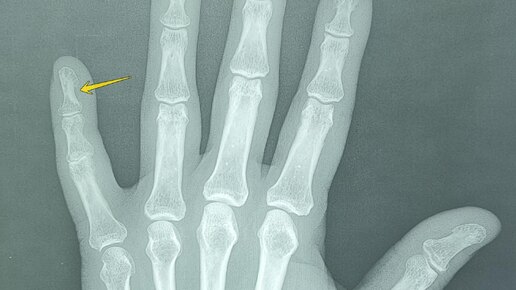

Эностоз-компактный островок остеосклероза.

Эностоз, или костный островок, представляет собой доброкачественное образование в костной ткани, которое обычно обнаруживается случайно при рентгенологическом исследовании. -Компактный костный островок(эностоз) дистальной фаланги пятого пальца правой кисти. Основные рентгенологические признаки эностоза включают: Эностоз необходимо дифференцировать с другими образованиями костной ткани, такими как: Для уточнения диагноза могут быть использованы дополнительные методы визуализации, такие как КТ или МРТ...